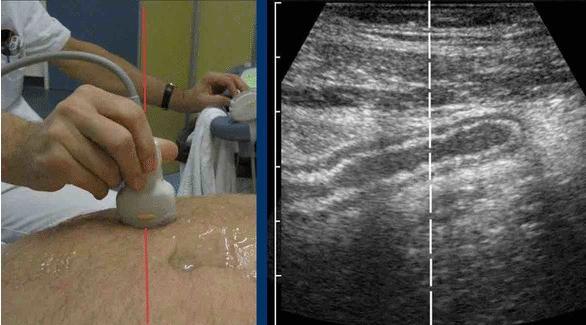

Để hiển thị một cấu trúc hình ống (ví dụ: ruột thừa viêm) trên hai mặt phẳng vuông góc, điều cần thiết là đưa cấu trúc đó vào mặt cắt ngang ở trung tâm hình ảnh siêu âm.

Điều này cho phép giữ cấu trúc trong tầm nhìn trong khi xoay đầu dò 90 độ (nhấp vào hình).

Nhẹ nhàng “lắc” đầu dò trong khi xoay giúp giữ cấu trúc hình ống nhỏ trong tầm quan sát.

Hình dạng khá bầu dục hơn là tròn của hầu hết các tay cầm đầu dò không thực sự thuận tiện cho việc thực hiện các chuyển động xoay tinh tế kết hợp với ép.

Hãy cố gắng phát triển cách cầm đầu dò cho phép bạn xoay từ cổ tay, không phải từ cánh tay hay vai, luôn cố gắng giữ trục đường đỏ.